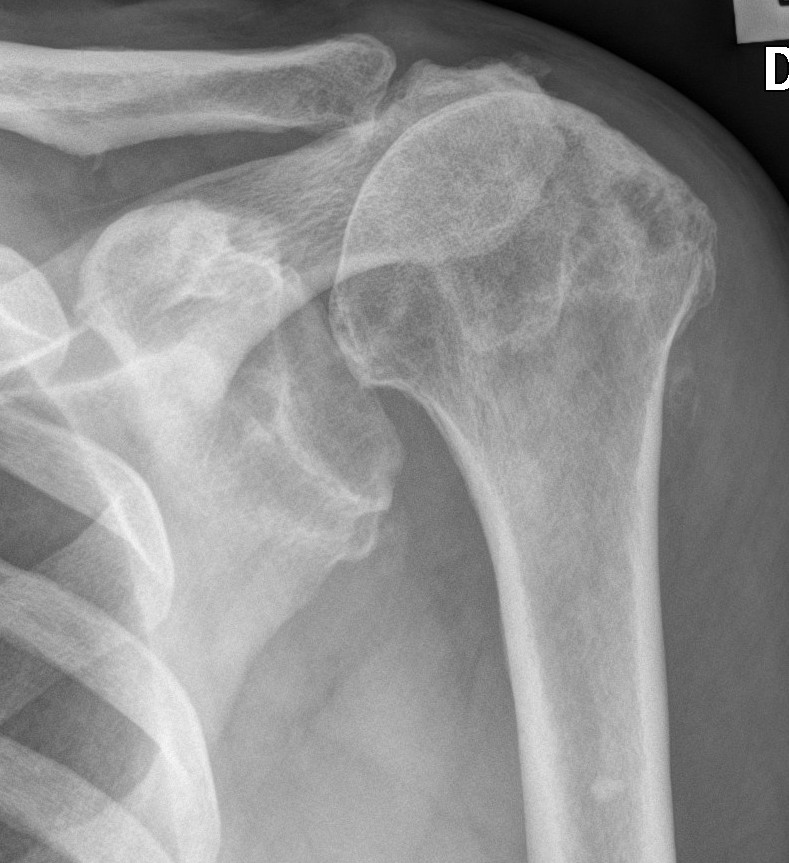

Xray

Typical changes of RA

- regional osteopenia

- marginal erosions and cysts

- humeral head erosions

- medial migration / protrusio